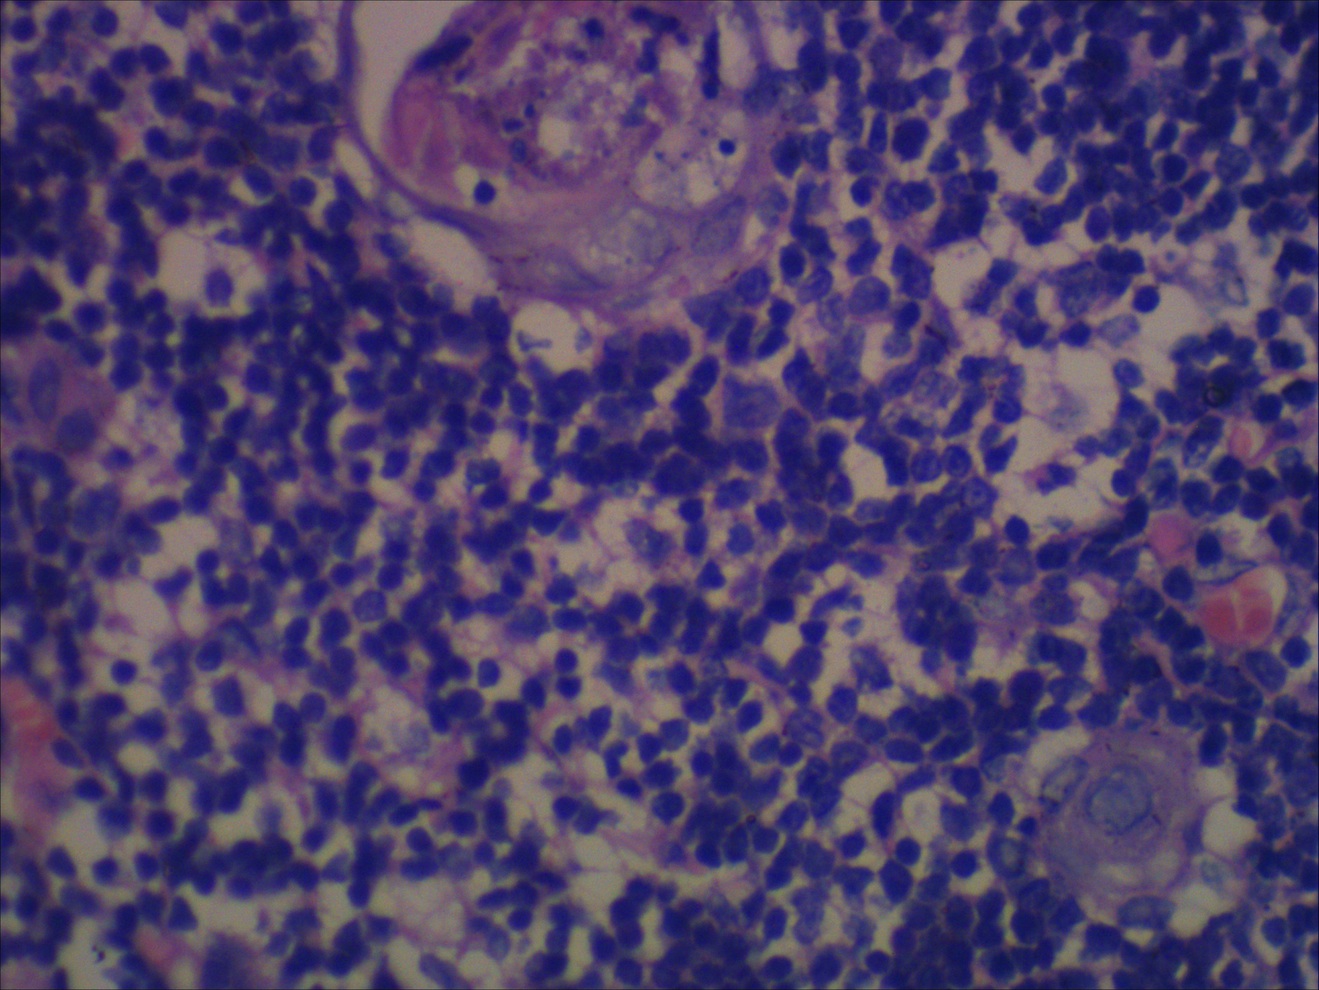

(A) Hyperplastic multinodular thymic parenchyma, separated by Thymic Hyperplasia Pathology Outlines Benign thymic gland (e.g., thymic follicular hyperplasia, true thymic hyperplasia, sampling bias): Defined as the presence of lymphoid follicles in the thymus regardless of the gland size. Thymomas are rare before 25 years of age but show a wide age. Uncommon disorder with no / limited symptoms; In fact, the gland is of normal size in. Thymomas are rare tumors. Thymic Hyperplasia Pathology Outlines.